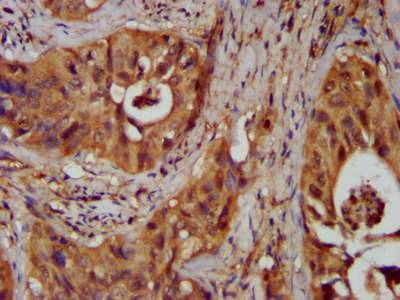

IHC image of CSB-PA015847LA01HU diluted at 1:300 and staining in paraffin-embedded human prostate cancer performed on a Leica BondTM system. After dewaxing and hydration, antigen retrieval was mediated by high pressure in a citrate buffer (pH 6.0). Section was blocked with 10% normal goat serum 30min at RT. Then primary antibody (1% BSA) was incubated at 4°C overnight. The primary is detected by a biotinylated secondary antibody and visualized using an HRP conjugated SP system.

IHC image of CSB-PA015847LA01HU diluted at 1:300 and staining in paraffin-embedded human cervical cancer performed on a Leica BondTM system. After dewaxing and hydration, antigen retrieval was mediated by high pressure in a citrate buffer (pH 6.0). Section was blocked with 10% normal goat serum 30min at RT. Then primary antibody (1% BSA) was incubated at 4°C overnight. The primary is detected by a biotinylated secondary antibody and visualized using an HRP conjugated SP system.